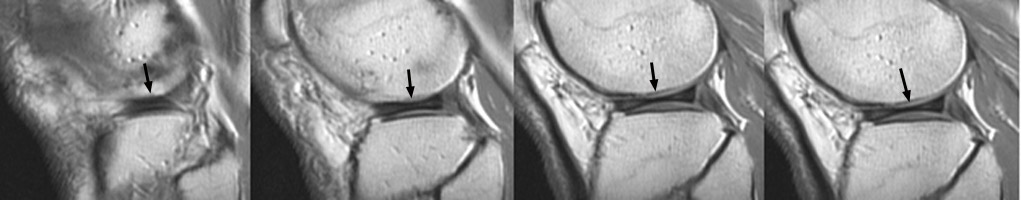

Seen on sagittal images, the bow-tie represents the continuity of the meniscus between the anterior and posterior horns. It is normally seen on 2 contiguous sagittal images. When it is seen on 3 or more contiguous 5 mm thick sagittal images is indicative of a discoid meniscus.

Discoid Meniscus - Click on the image for a larger version